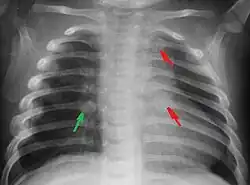

Most nations with child abuse laws deem the deliberate infliction of serious injuries, or actions that place the child at obvious risk of serious injury or death, to be illegal.[36] Bruises, scratches, burns, broken bones, lacerations—as well as repeated "mishaps", and rough treatment that could cause physical injuries—can be physical abuse.[37] Multiple injuries or fractures at different stages of healing can raise suspicion of abuse.

C. Henry Kempe and his colleagues were the first to describe the battered-child syndrome in 1962.[40] The battered-child syndrome is a term used to describe a collection of injuries that young children sustain as a result of repeated physical abuse or neglect.[41][42] These symptoms may include: fractures of bones, multiple soft tissue injuries, subdural hematoma (bleeding in the brain), malnutrition, and poor skin hygiene.[42][43]

The immediate physical effects of abuse or neglect can be relatively minor (bruises or cuts) or severe (broken bones, hemorrhage, death). Certain injuries, such as rib fractures or femoral fractures in infants that are not yet walking, may increase suspicion of child physical abuse, although such injuries are only seen in a fraction of children suffering physical abuse.[90][91] Cigarette burns or scald injuries may also prompt evaluation for child physical abuse.[92]

Suspicion for physical abuse is recommended when injuries occur in a child who is not yet able to walk independently.[162] Additionally, having multiple injuries that are in different stages of healing and having injuries in unusual location, such as the torso, ears, face, or neck, may prompt evaluation for child abuse.[162] Medical professionals may also become suspicious of child abuse when a caregiver is not able to provide an explanation for an injury that is consistent with the type or severity of the injury.[163]